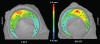

Materials and methods: Four fresh-frozen cadaver hip joints from two male donors, ages 43 and 46 years, were obtained; institutional review board approval for cadaver research was also obtained. Sixteen holes were drilled perpendicular to the cartilage of four cadaveric acetabula (two specimens). Hip capsules were surgically closed, injected with contrast material, and scanned by using multidetector CT. After scanning, 5.3-mmcores were harvested concentrically at each drill hole and cartilage thickness was measured with a microscope. Cartilage was reconstructed in 3D by using commercial software. Segmentations were repeated by two authors. Reconstructed cartilage thickness was determined by using a published algorithm. Bland-Altman plots and linear regression were used to assess accuracy. Repeatability was quantified by using the coefficient of variation, intraclass correlation coefficient (ICC), repeatability coefficient, and percentage variability.

Results: Cartilage was reconstructed to a bias of -0.13 mm and a repeatability coefficient of + or - 0.46 mm. Regression of the scatterplots indicated a tendency for multidetector CT to overestimate thickness. Intra- and interobserver repeatability were very good. For intraobserver correlation, the coefficient of variation was 14.80%, the ICC was 0.88, the repeatability coefficient was 0.55 mm, and the percentage variability was 11.77%. For interobserver correlation, the coefficient of variation was 13.47%, the ICC was 0.90, the repeatability coefficient was 0.52 mm, and the percentage variability was 11.63%.